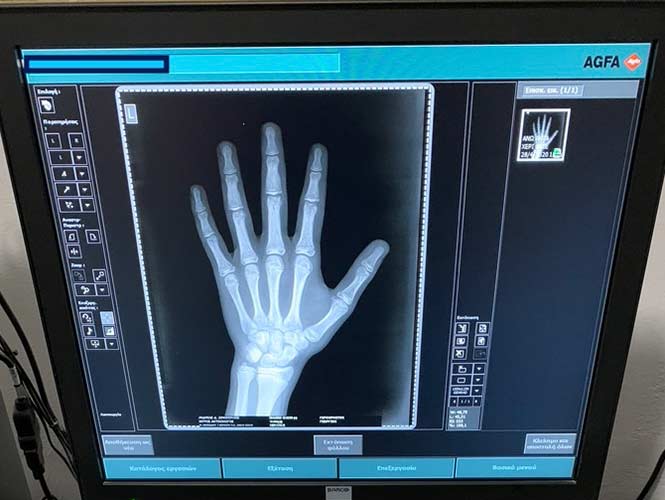

Στο Ιατρείο διενεργούνται επίσης όλες οι ακτινογραφίες σε νεογνά, βρέφη και παιδιά με κατάλληλα πρωτόκολλα, καθώς και σε ενηλίκους. Ο εξοπλισμός του Ακτινολογικού περιλαμβάνει τελευταίας τεχνολογίας σύστημα ψηφιοποίησης της εταιρίας AGFA Healthcare, με τα πλεονεκτήματα της ψηφιακής επεξεργασίας των ακτινογραφιών, της αποφυγής επαναλήψεων και με αυτόν τον τρόπο μείωση της δόσης Ακτινοβολίας καθώς και τη δυνατότητα εγγραφής των Ακτινογραφιών σε CD-usb ή σε Ακτινολογικό φίλμ, ανάλογα με την επιθυμία του εξεταζομένου.